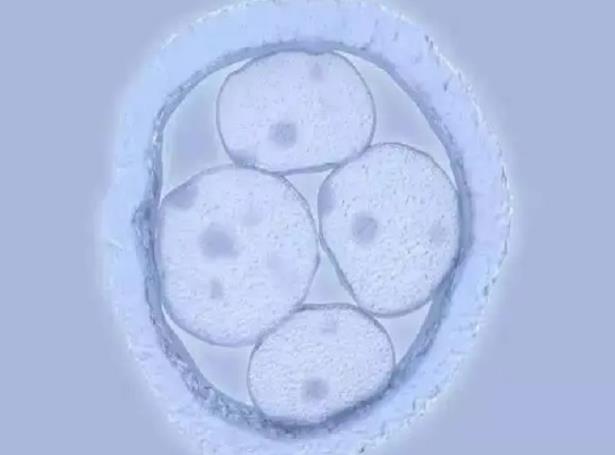

2、胚胎质量:不好的胚胎不容易成功,优质的胚胎容易成功。一个好的胚胎与男女双方的精子和卵子质量密切相关。